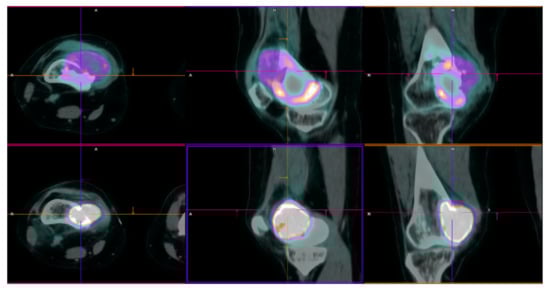

2.1. Patient 1

2.2. Patient 2

2.3. Patient 3

| Age | Sex | ECOG PS | Diagnosis (Date) | Site of Primary GCTB | Surgery | Rec. Date | Treat. Management | Malignant Transformation (Date/Surgery or Biopsy) | Treat. | Evolution | Subsequent CHT Lines | FU/D | Time to MT (Months) | OS from GCTB Diagnosis (Months) | OS from MT (Months) | |

|---|---|---|---|---|---|---|---|---|---|---|---|---|---|---|---|---|

| Pt 1 | 29 | F | 0 | 17 July | Right femur | Curettage and bone grafts | 18 February | Neoadj denosumab (7 cycles) | 18 July Extraarticular resection: high-grade fibroblastic osteosarcoma | ISG/OS-2 | PD | I: IFO II: GEM.TXT III: PAZO | D 22 January | 9 | 53 | 43 |

| Pt 2 | 48 | M | 0 | 16 November | Right tibia | Curettage and bone grafts | 20 October | Neoadj denosumab (6 cycles) | 21 February Extraarticular resection: malignant transformation of GCTB | EURO BOSS | NED | - | FU 21 December | 51 | 64 | 13 |

| Pt 3 | 20 | F | 0 | 10 September | Left femur | Resection of the femoral head, curettage and bone grafts | 11 March | Biopsy | 11 June Biopsy: high-grade osteosarcoma G3 with aberrant expression of beta-HCG | ISG/OS-1 | PD | - | D 11 November | 9 | 14 | 5 |